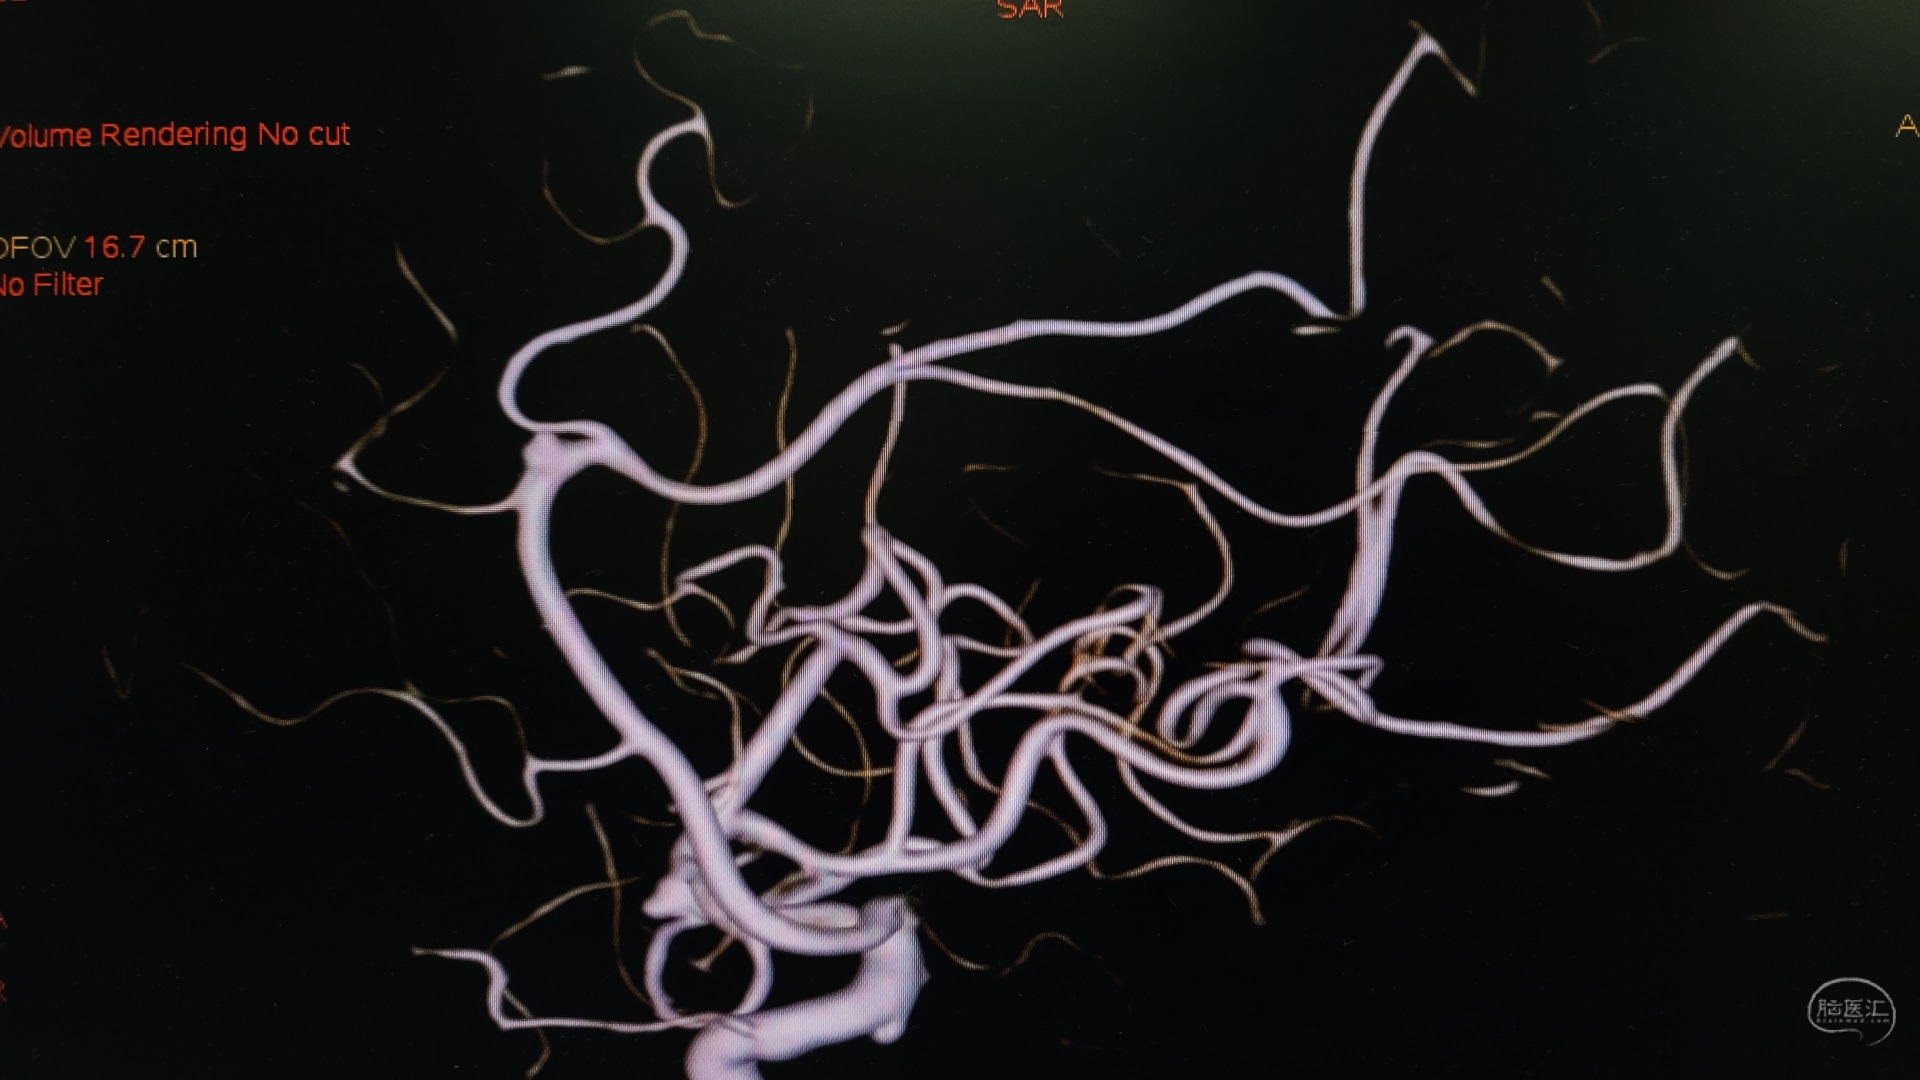

造影显示颅内多发动脉瘤:右侧大脑中动脉瘤;右侧A2-A3交界处动脉瘤;右侧后交通可疑动脉瘤。

右侧大脑中动脉瘤位于分叉部。

右侧A2/A3动脉瘤近端有一分支血管。

如图所示:显露动脉瘤及载瘤动脉及分支的关系